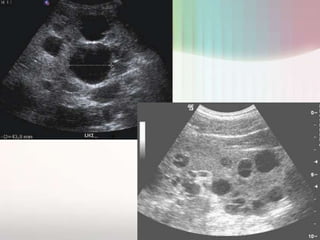

•Está recomendada en el dx inicial.

ECOGRAFÍA      •permite diferenciar la ubicación, tamaño y número de

abscesos, colecciones ≥ 1,5 cm.

HEPÁTICA      •lesiones únicas de formas oval o redondeada, bordes bien

definidos, hipoecogénicos y cerca de la superficie

La ecografía y la TAC representan los métodos de elección

para el diagnóstico.

Ecogragfía

• Imágenes quísticas de diferente tamaño, anecoicas, de forma

redondeada u oval y márgenes bien delimitados